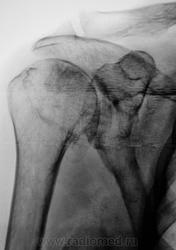

Жалобы на длительные боли в плечевом суставе

Таков артроз.

Смущает дополнительный "контур" по стрелкам.

Думаю,что это "неодокостеневшие" костные разрастания(не знаю,как точно обозвать).

ДОА.

Что в анамнезе? Была травма? После чего боли появились. Что можно сказать об объёме движений? Мне кажется, что изменения связаны с обызвествлением суставной сумки.

Боли в течение последних двух - трёх лет. Четко (при разговоре) травму вспомнить не может, хотя жительница сельской местности, где травмой считается, ну минимум перелом.

Мне кажется, что изменения связаны с обызвествлением суставной сумки.

Мне тоже так показалось.